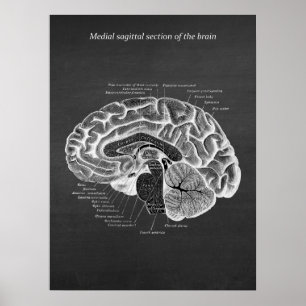

Brain Anatomical Illustration Print no. 3

Price$95.40